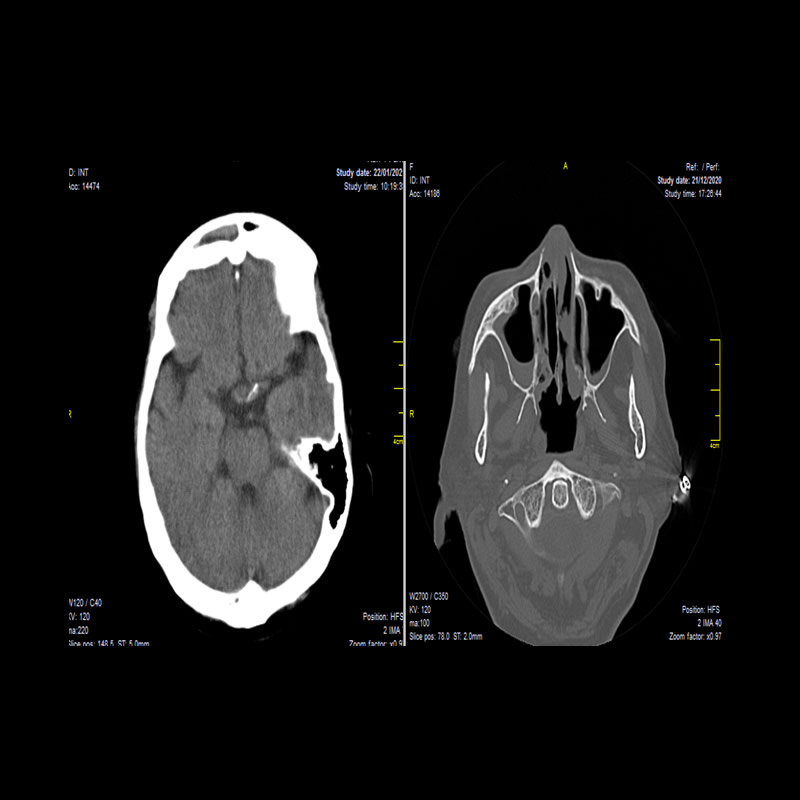

Abril 2021. Instituto Roentgen Paciente de sexo femenino 75 años MC: Ptosis palpebral derecha y parálisis ocular homolateral